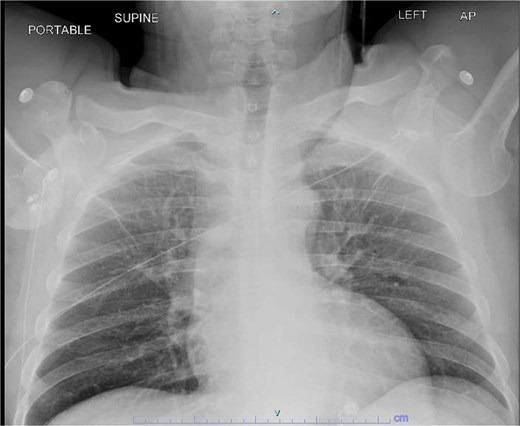

A 59-year-old right-hand–dominant male with history of prior right rotator cuff repair presented to the emergency department after a workplace injury in which four 60-lb pallets fell onto his upper back, while he was operating the steering wheel of a pallet jack. He arrived with both upper extremities locked in overhead abduction, reporting bilateral shoulder pain and hand paresthesias (Fig. 1).

Both shoulders were reduced urgently by the orthopedic team, with immediate improvement in paresthesias (Fig. 2). Post-reduction CTs were significant for bilateral chronic rotator cuff disease with superior migration of the humeral heads, right-sided supraspinatus and subscapularis atrophy, and a left nondisplaced glenoid fracture (Figs 3 and 4). He was discharged home in bilateral slings.

Post-reduction X-rays demonstrating congruency restored to right and left glenohumeral joints, with evidence of superior humeral head migration bilaterally.